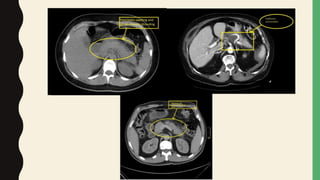

Computed Tomography

• Routine CT with IV/O contrast- not recommended

– Most have uncomplicated disease

– No evidence that early CT improves clinical outcome- probably CT findings are delayed &

may underestimate disease severity

– Early detection of peripancreatic fluid collection or pancreatic necrosis with in first few days-

require no Rx

– Complete extent of local complications is usually not appreciated until at least 3 days after

onset of symptoms (false negative in too early disease)

– IV contrast- allergic reactions, nephrotoxicity & worsening of pancreatitis

• If clinical diagnosis is in doubt- consider further evaluation with IV contrast abdominal

CT

– Pancreatic parenchymal inflammation +/- peripancreatic fat inflammation

– Pancreatic parenchymal necrosis or peripancreatic necrosis

– Peripancreatic fluid collection

– Pancreatic pseudocyst